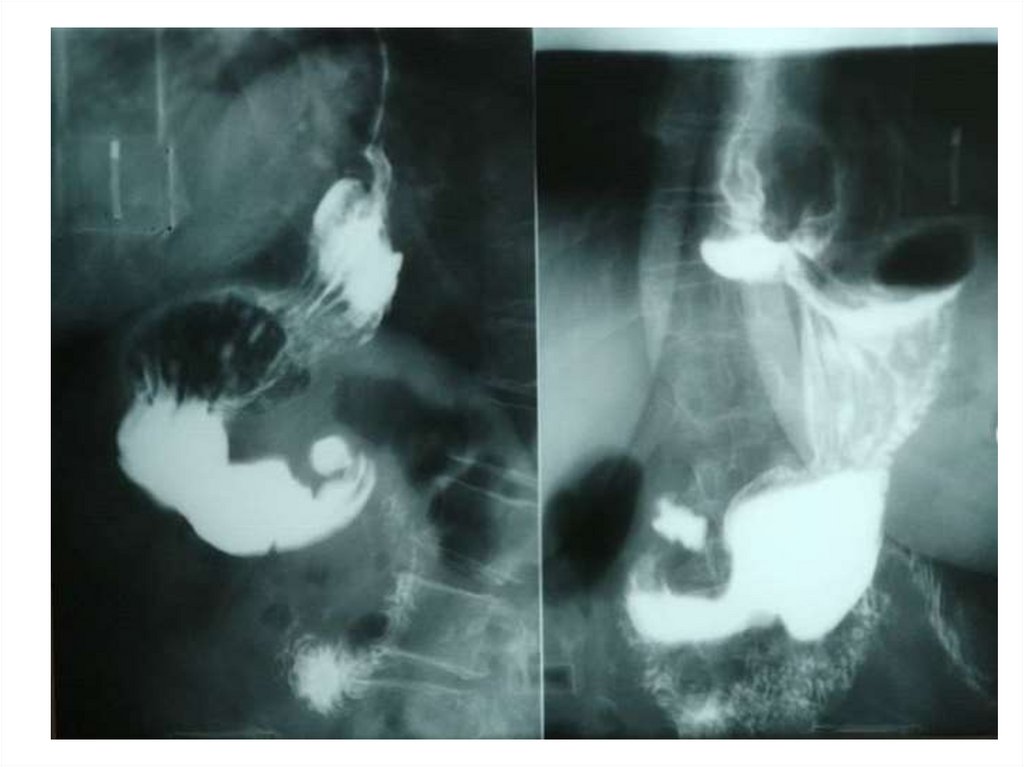

Назовите

• Вид исследования

• Область исследования

• Патологию